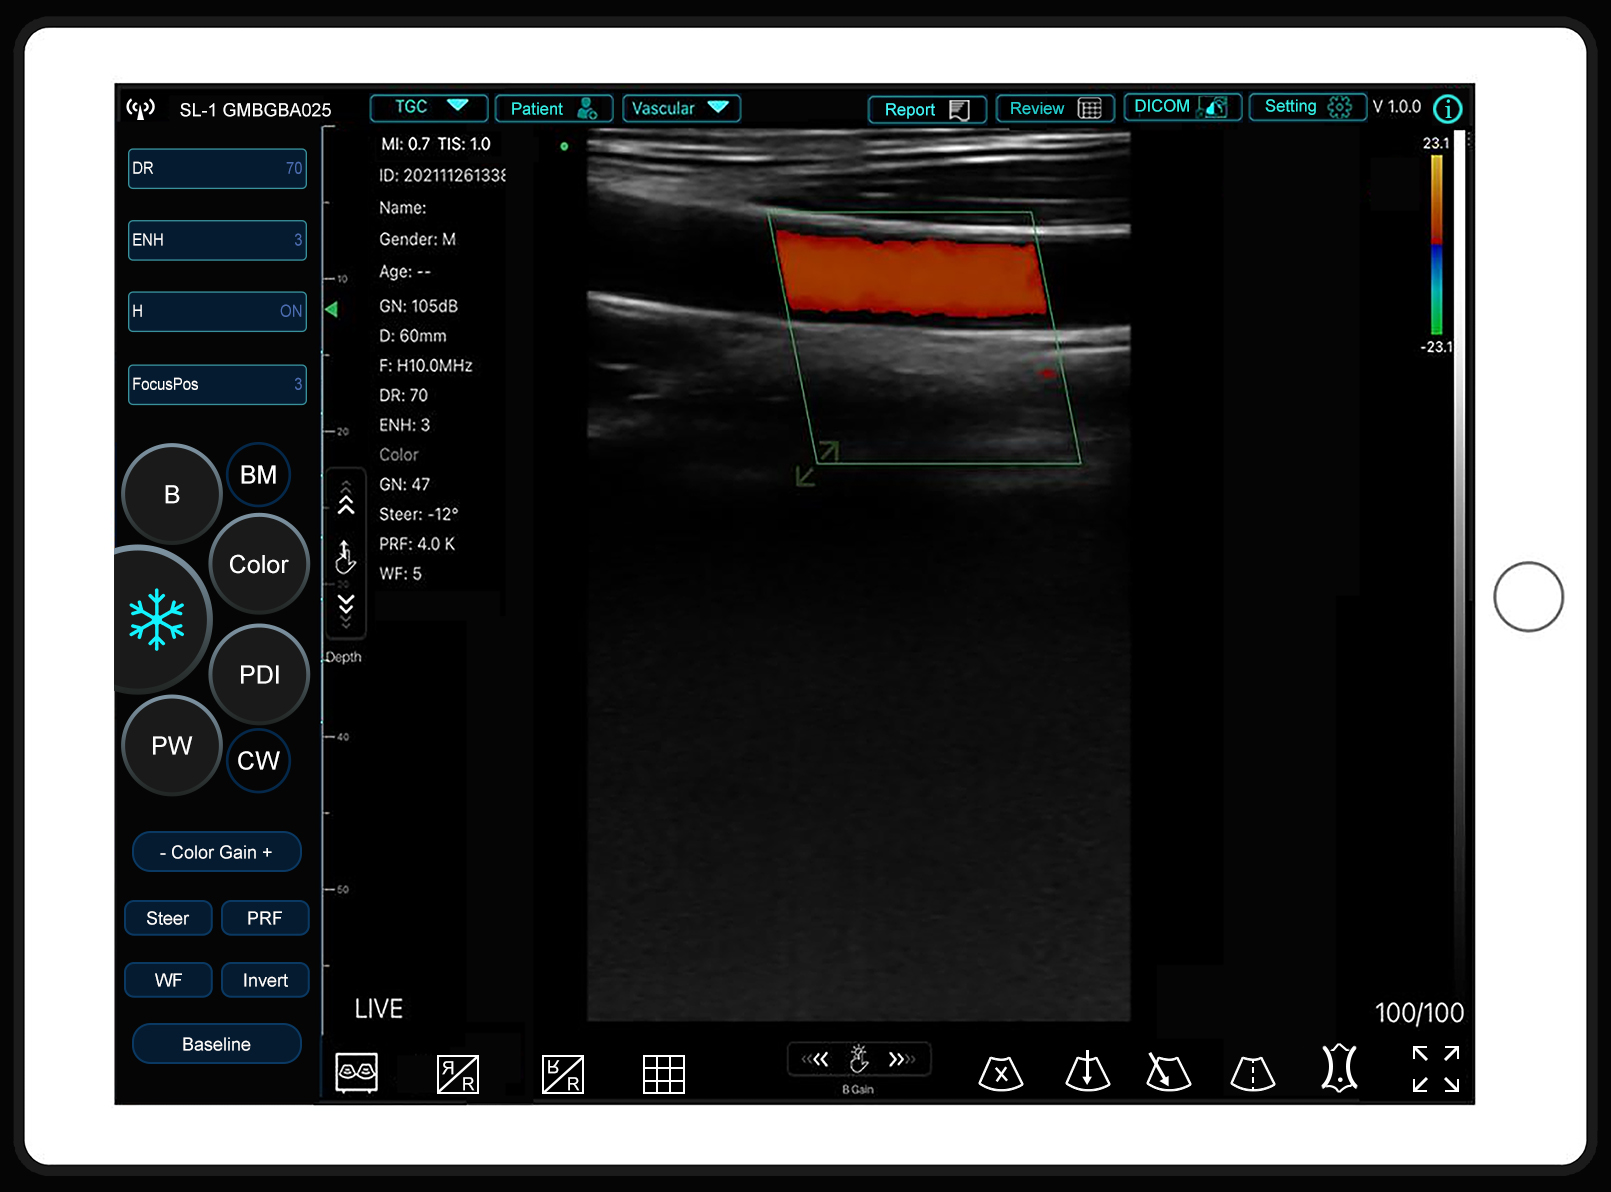

Sonostar has released a new APP called SmartUSG

Sonostar has released a new APP called SmartUSG.The interface of the new APP is more attractive andVIEW MORE →2026-03-18 -